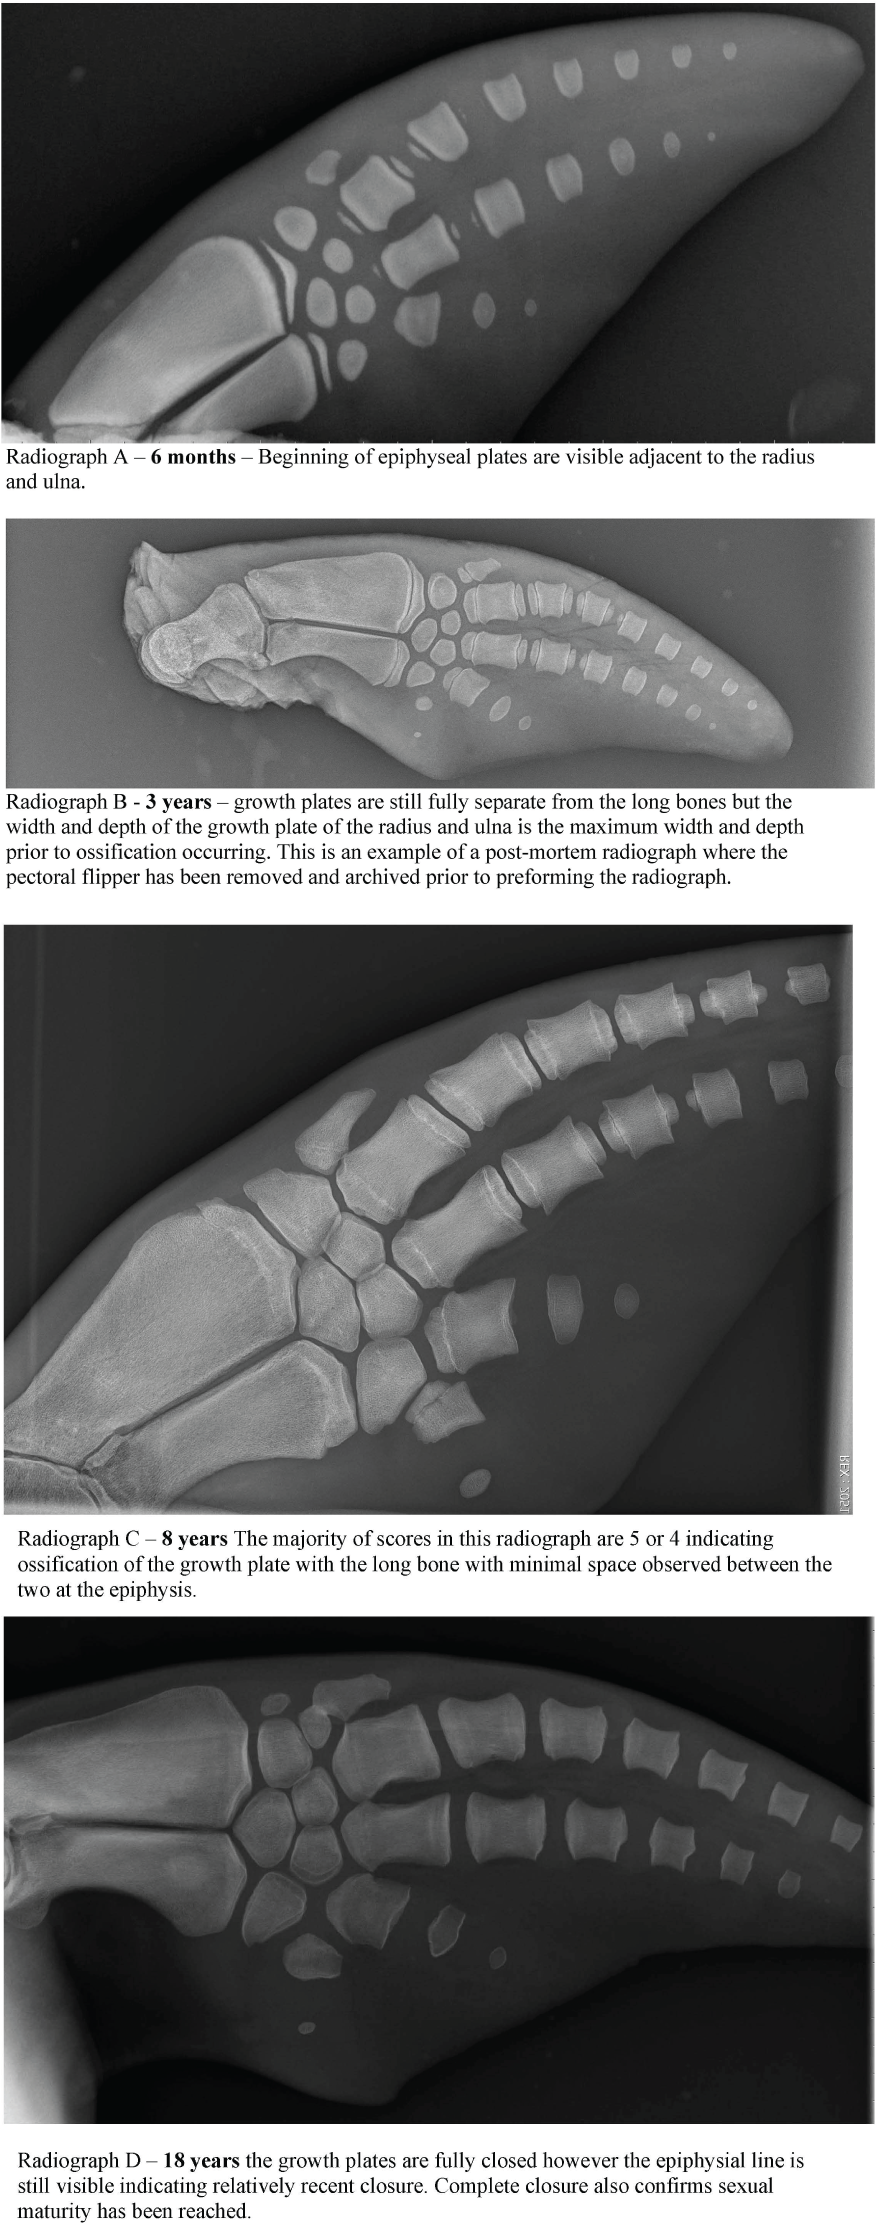

Validation of the GLG technique has not previously been possible in dolphins over 16 years of age due to a lack of samples available from known aged dolphins (Hohn et al., 1989). Despite the well-documented limitations of tooth aging, GLG tooth aging remains the primary method to estimate the age of wild bottlenose dolphins due to the insufficiency of alternative aging techniques. Alternative methods to estimate age have included morphometrics such as total straight length, however the asymptotic nature of dolphin growth curves results in length being an inaccurate assessment of age in older animals (Mcfee et al., 2012). More recently, dental radiography was demonstrated as a viable alternative to tooth extraction, however accuracy in age estimation decreased significantly in dolphins > 11 years of age, therefore this technique could not be used across the dolphin’s full lifespan (Herrman et al., 2020). Bone density was extensively researched but unfortunately did not provide an accurate correlation with age (Powell et al., 2019). Pectoral flipper radiography is highly accurate in young animals up to adulthood, but relies upon degenerative osteoarthritic changes to accurately estimate age in older individuals when all bone growth plates are fully consolidated. Therefore flipper radiography becomes more subjective in dolphins >25 years of age (Barratclough et al., 2019a) (Figure 3). Epigenetics via DNA methylation is a promising new technology to accurately estimate age, and may be applicable across the dolphin’s lifespan (Barratclough et al., 2021; Peters et al., 2022).

Figure 3 A pectoral flipper radiograph demonstrating the open physeal plates present in a young sexually immature dolphin. The scores for each of the 16 locations are provided on the radiograph. L, Left pectoral flipper.

A total of 37 pectoral flipper radiographs (PFR) were obtained from 36 dolphins; 12 from MMP dolphins, 10 from Sarasota health assessments and 15 from stranded dolphins in Sarasota Bay, following previously published techniques (Barratclough et al., 2019a). Radiographs can be taken of either flipper and a dorsal ventral view of the flipper including the distal radius to the distal phalanges (Figure 2). Of the 37 radiographs 13 were from females and 24 were from males. Of the 12 MMP dolphins, nine were known age from observed birth. Two had age estimated between 2-4 years of age based on morphometrics at the time of acquisition and one animal was estimated as 3yrs by GLG. Of the 25 Sarasota cases, 20 were known age from observed birth and five were known minimum age. In addition, 10 pectoral flipper radiographs were taken during 2019 and 2022 Sarasota Bay live dolphin health assessments, with one individual radiographed in both 2019 and 2022. Nine of these cases had known age and one individual was known minimum age. Of the 15 stranded cases, six were of known age and four had previous sighting data providing a minimum age estimate. Figure 4 depicts four radiographs with suggested scores for the growth plates and the given ages of the different stages allowing depiction of the predicted sequential changes in growth plate closure over time.

Radiographs were obtained as part of routine animal care under the authorization of U.S. Code, Title 10, USC 7524. Secretary of Navy Instruction 3900.41H directs that Navy marine mammals be provided the highest quality of care. The U.S. Navy Marine Mammal Program (MMP), Naval Information Warfare Center (NIWC) Pacific, houses and cares for a population of bottlenose dolphins and California sea lions in San Diego Bay (CA, USA). The MMP is accredited by AAALAC International and adheres to the national standards of the U.S. Public Health Service Policy on the Humane Care and Use of Laboratory Animals and the Animal Welfare Act. Pectoral flipper bone maturation scores were assigned independently by two blind reviewers, both marine mammal veterinarians with experience of the previously published technique (A.Barratclough and D. Garcia-Parraga). The established methodology requires a score of -1 to 8 to be applied to 16 different anatomic locations within the pectoral flipper with each score denoting the degree of development of the growth plate (Barratclough et al., 2019a). The metaphyseal region of the radius and ulna are the most informative along with the proximal and distal epiphysis of metacarpals II and III. The sex-specific equations reported by Barratclough et al. (2019a) were applied to predict the chronological age:

Sex-specific equations are required due to the different growth rates between male and female bottlenose dolphins and the different ages at which sexual and skeletal maturity occur. For example closure of the female radius growth plate is expected at 6-8 years whereas in males this does not occur until 10-12 years. By including 16 different scoring locations, the accuracy of age prediction is improved. Scores from the two reviewers were combined to provide an average age estimation for each individual. The known ages of the animals included for pectoral radiographs ranged from 0 – 58 years of age.